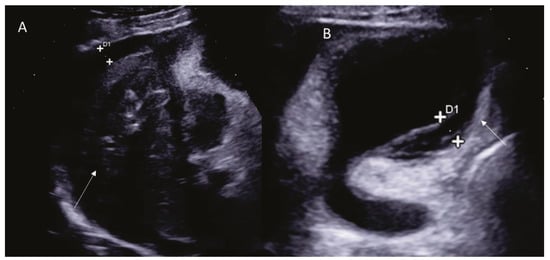

- Sugihara, T.; Koda, M.; Tokunaga, S.; Matono, T.; Nagahara, T.; Ueki, M.; Murawaki, Y.; Kaminou, T. Contrast-enhanced ultrasonography revealed active thoracic bleeding. J. Med. Ultrason. 2010, 37, 143–145. [Google Scholar] [CrossRef] [PubMed]

- Catalano, O.; Sandomenico, F.; Raso, M.M.; Siani, A. Real-time, contrast-enhanced sonography: A new tool for detecting active bleeding. J. Trauma Inj. Infect. Crit. Care 2005, 59, 933–939. [Google Scholar] [CrossRef] [PubMed]

- Francica, G.; Meloni, M.F.; Riccardi, L.; Giangregorio, F.; Caturelli, E.; Terracciano, F.; de Sio, I. Role of Contrast-Enhanced Ultrasound in the Detection of Complications After Ultrasound-Guided Liver Interventional Procedures. J. Ultrasound Med. 2020, 40, 1665–1673. [Google Scholar] [CrossRef] [PubMed]